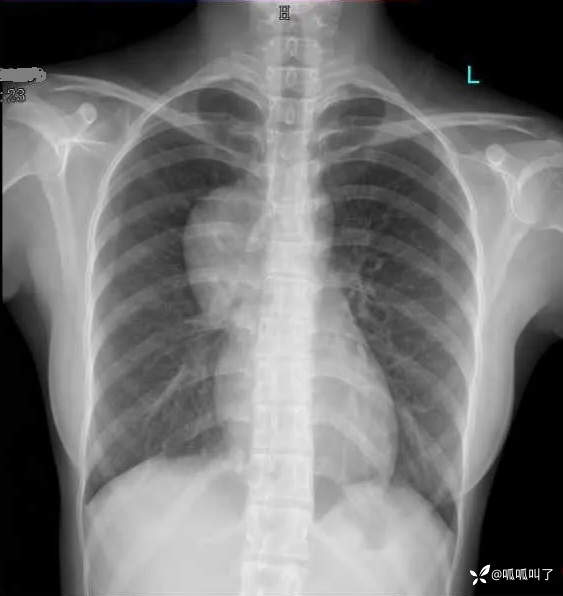

病史:女,17岁,高中学生,学校体检发现纵隔肿物,平素无明显不适症状,建议进一步检查,次日就诊于当地医院行胸部CT提示“右肺下叶脊柱旁占位”,建议入院治疗,后就诊于我院。

既往史:曾患先天性白内障并手术治疗。

DR